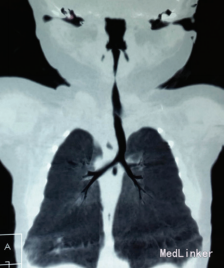

出院后5 d患儿再次因吸气性喉梗阻、发绀就诊,予急诊喉部CT,多平面重建后发现患儿声门下气道异常狭窄,三维重建后甚至见气道连续性中断,考虑为喉软化致吸气性梗阻,大气道塌陷所致。诊断为喉软化症,予雾化及抗炎治疗后病情很快缓解。建议转上级医院治疗。患儿上级医院继续保守治疗后出院,此后有反复发作,每次发作后予抗感染及布地奈德雾化处理后好转。目前患儿已6个月,喉喘鸣症状轻微。 讨论:喉软骨软化症是引起新生儿喉喘鸣最常见的原因,该病易导致吸入性肺炎、反复呼吸道感染,病程长,影响小儿营养,易致营养不良等。